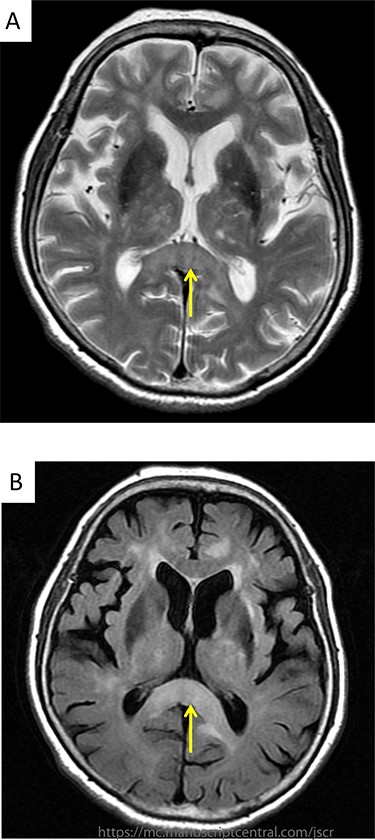

(A) Brain MRI revealed hyperintensity signals on T2-weighted image at the splenium of the corpus callosum; (B) brain MRI revealed hyperintensity signals on FLAIR images at the same region.

A 80-year- Japanese woman first visited our hospital in March 2017 with several neurological symptoms such as headache, incontinence, wobble and consciousness disorder (Glasgow Coma Scale: 14). She was a smoker (from 18 to 80 years of age, one pack per day, Brinkman Index: 1240) and had no family history of malignancies. Brain magnetic resonance imaging (MRI) revealed hyperintense signals on T2-weighted (Fig. 1A) and fluid attenuation inversion recovery (FLAIR) images at the splenium of the corpus callosum (Fig. 1B). These findings were compatible with limbic encephalitis. A cerebrospinal fluid analysis showed inflammation with negative cytology, and an electroencephalogram demonstrated normal study. Because PLE due to malignant tumor was suspected, a systemic examination was performed. Chest computed tomography (CT) detected a nodule with an irregular margin measuring 17 × 14 mm in size at the subpleural area of the left upper lobe S3 of the lung (Fig. 2). The enhanced systemic CT and brain MRI detected neither regional lymph node swelling nor distant metastases, and then it was classified as clinical stage T1bN0M0 according to the eighth edition of the TNM classification by International Association for the Study of Lung Cancer (IASLC). Her conscious level was worsening (Glasgow Coma Scale: 5). After obtaining informed consent, lung partial resection was performed via video-assisted thoracic surgery (VATS). The permanent pathological examination revealed squamous cell carcinoma (keratinizing type) (Fig. 3), and it was classified as pathological stage T1bN0M0. Anti-Hu antibody, one of onconeural antibodies, was investigated as part of the workup for PLE, but the result was negative. Her post-operative course was uneventful, but she died 50 days after surgery caused by the rapid progression of encephalitis.